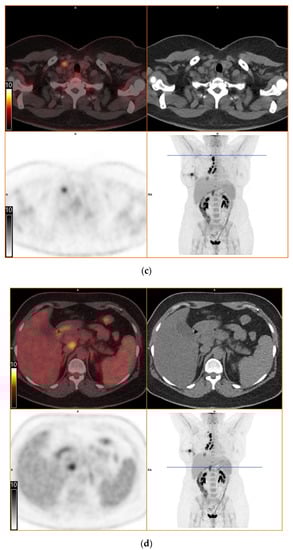

To further evaluate the suspected malignant disease, a [18F]FDG-PET/CT was performed (day +14). It detected multiple hypermetabolic lymph nodes of up to 33 mm in diameter, located right interlobar, at the right hilus, the mediastinum and right supraclavicular. The previously known lesion of the right lung showed only moderate metabolic activity. In addition, a moderately active precaval lymph node was detected (Figure 1).

Figure 1.

[18F]FDG-PET/CT. Upper left: PET and CT fusion images. Upper right: CT images. Lower left: PET images. Lower right: Maximum intensity projection. Blue line: Axial imaging level. Scale bars: Standardized uptake value. Star: Postinterventional diffuse uptake of the right thoracic wall after chest tube placement. (a) Moderate uptake in a solitary solid pulmonary lesion with irregular margins in the right lower lobe of the lung (b) Greater uptake in the draining lymph nodes right interlobar, right hilar and mediastinal (c) A further draining right supraclavicular lymph node showing high uptake as well (d) Moderate uptake in a precaval abdominal lymph node.